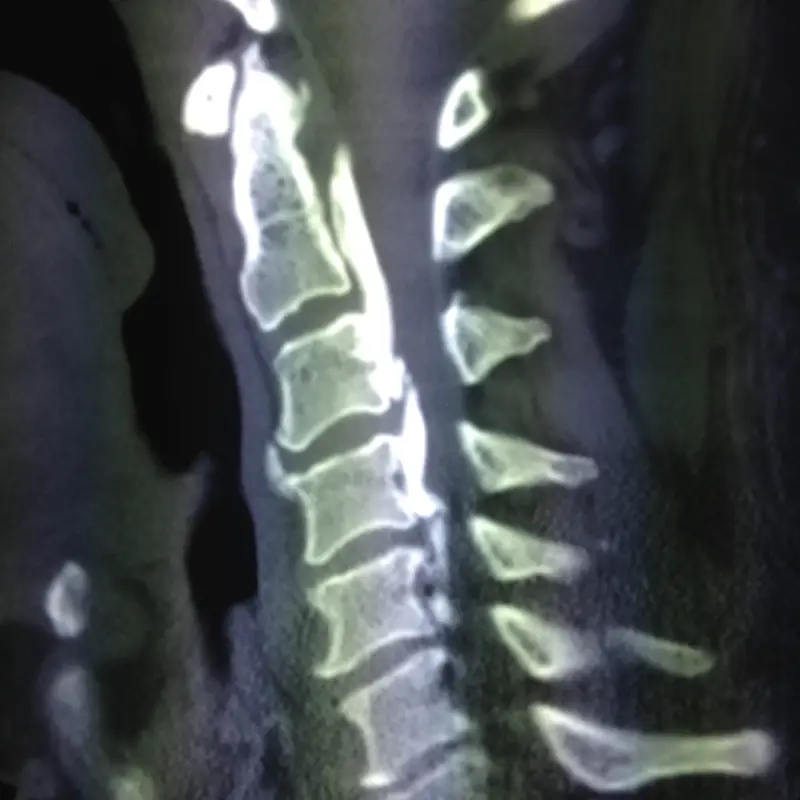

Ct Showing Ossified Posterior Longitudinal Ligament (OPLL)

Ossified Posterior Longitudinal Ligament (OPLL)